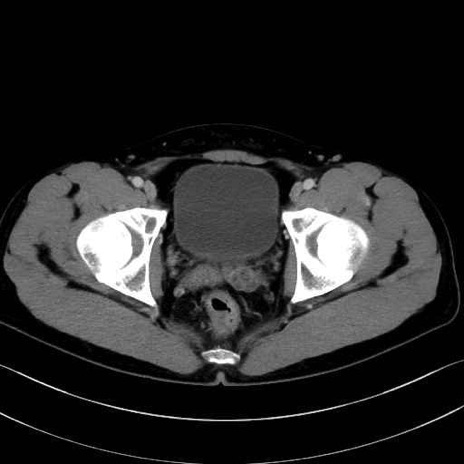

肛門挙筋 (Levator ani)